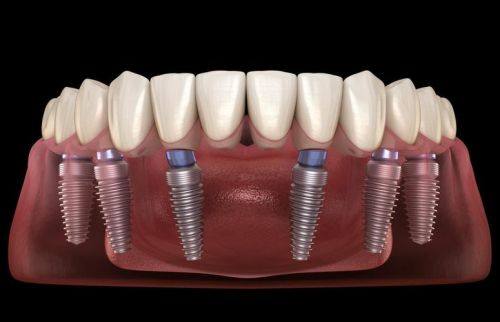

活动义齿一般多少钱一颗费用?2026年最新价格揭秘! 文章揭秘2026年活动义齿最新价格。通常镶活动假牙一颗1000 - 3000元,不同类型费用有别。如隐形义齿1000 - 1200元,便宜但寿命短、咀嚼差;钴铬合金等1500 - 2000元,强度好、使用久;纯钛基托2000 - 3000元,舒适美观。此外,地区、医院等级和医生水平也影响价格,选义齿要综合考量。 活动义齿 2026年03月04日 0 点赞 0 评论 7 浏览

活动义齿哪种最舒服还不伤害基牙?揭秘3种最佳选择! 本文围绕“活动义齿哪种最舒服还不伤害基牙”展开。首先强调了活动义齿舒适与护基牙的重要性,接着介绍了纯钛金属基托活动义齿等三种义齿的特点,包括舒适度、对基牙的影响、价格等。还给出选择建议,要考虑口腔状况、经济因素,并听取医生建议。最后提醒佩戴后注意适应期、清洁和饮食,综合考量选适合自己的义齿。 活动义齿 2026年03月04日 0 点赞 0 评论 12 浏览

补一颗活动义齿多少钱?揭秘真实费用与选择技巧! 本文围绕补一颗活动义齿的费用及选择技巧展开。费用大致在100 - 300元,受材料、修复难易、医院级别、当地经济等因素影响。不同材料义齿各有特点和价格区间。选择时要综合自身情况,选正规机构,多对比。此外,后期维护有成本,需正确佩戴清洁。提醒大家综合考量价格、质量和舒适度,必要时咨询医生。 活动义齿 2026年03月04日 0 点赞 0 评论 7 浏览